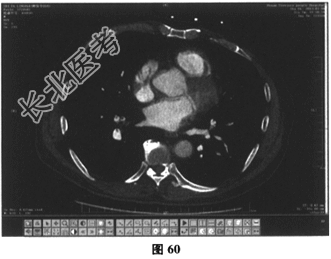

- 多项选择题5.[提示]患者肺动脉CTA(图57~图60):右肺中动脉及右下肺动脉低密度充盈缺损。下肢静脉多普勒超声未见异常。综合上述检查结果, 明确诊断为

A、肺栓塞